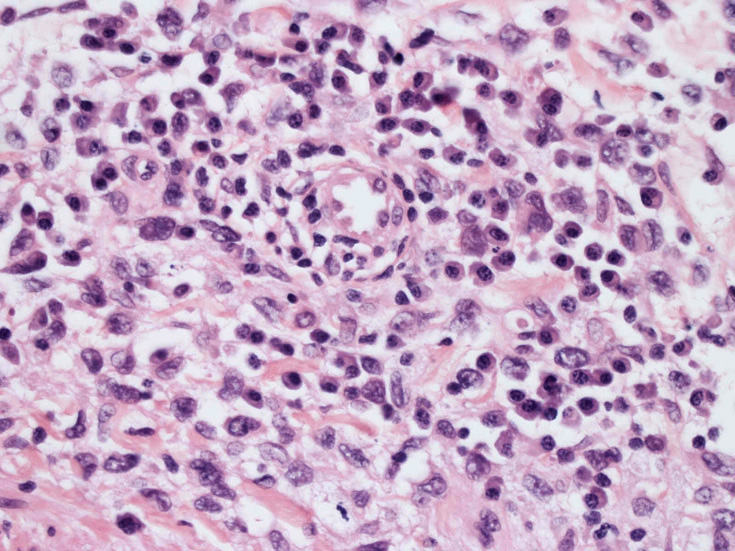

LCSの病理組織所見

Langerhans cell histiocytosisの高悪性度 variantで明らかな悪性像を示すLangerhans cellの腫瘍性増殖と定義される(WHO, 2008)

大型細胞の増殖よりなる腫瘍。縦溝,しわ,切れ込みのある核をもった大型細胞も出現する。クロマチンは顆粒状で核小体も明瞭である。核分裂は >50/10hpfと多い。eosinophilsは少ない。壊死が多発することがある。未分化ないし低分化な細胞像, 組織所見のため鑑別診断は多岐にわたり、的確な免疫染色を行う必要がある。

皮膚に異型細胞の浸潤がみられる。異型細胞は表皮内に浸潤するほか、表皮真皮境界部, 真皮, 皮下脂肪組織にもびまん, 結節様の浸潤所見を示す。血管周囲に浸潤、集蔟する所見も多く見られる。 増殖浸潤細胞の核には類円形や腎臓形, またはへこみ, 切れ込み, 溝などを有する多型な核が認められる。クロマチンは粗でvesicularな核が多い。核小体の明らかな核もある。好エオジン性の核内封入体様構造も少数に見られた。mitosisは容易に認められる。hyperchromaticな多型核, bizzarreな細胞が高頻度に認められ異型度は高いと考えられる。細胞質は境界不明瞭, 淡明または泡沫様の 好エオジン性胞体である。